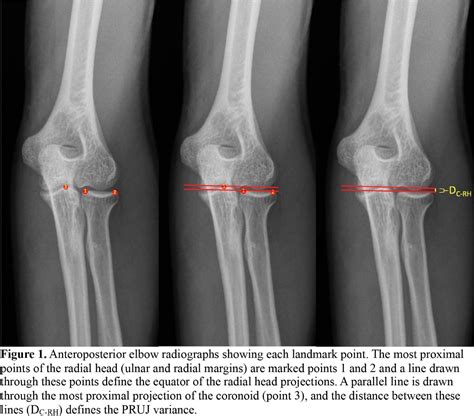

Diagnosing issues related to the Proximal Radioulnar Joint typically involves a combination of clinical examination and imaging studies. A thorough medical history and physical examination can help identify the underlying cause of symptoms. Imaging studies, such as X-rays, CT scans, and MRI, provide detailed views of the joint and surrounding structures, aiding in accurate diagnosis.